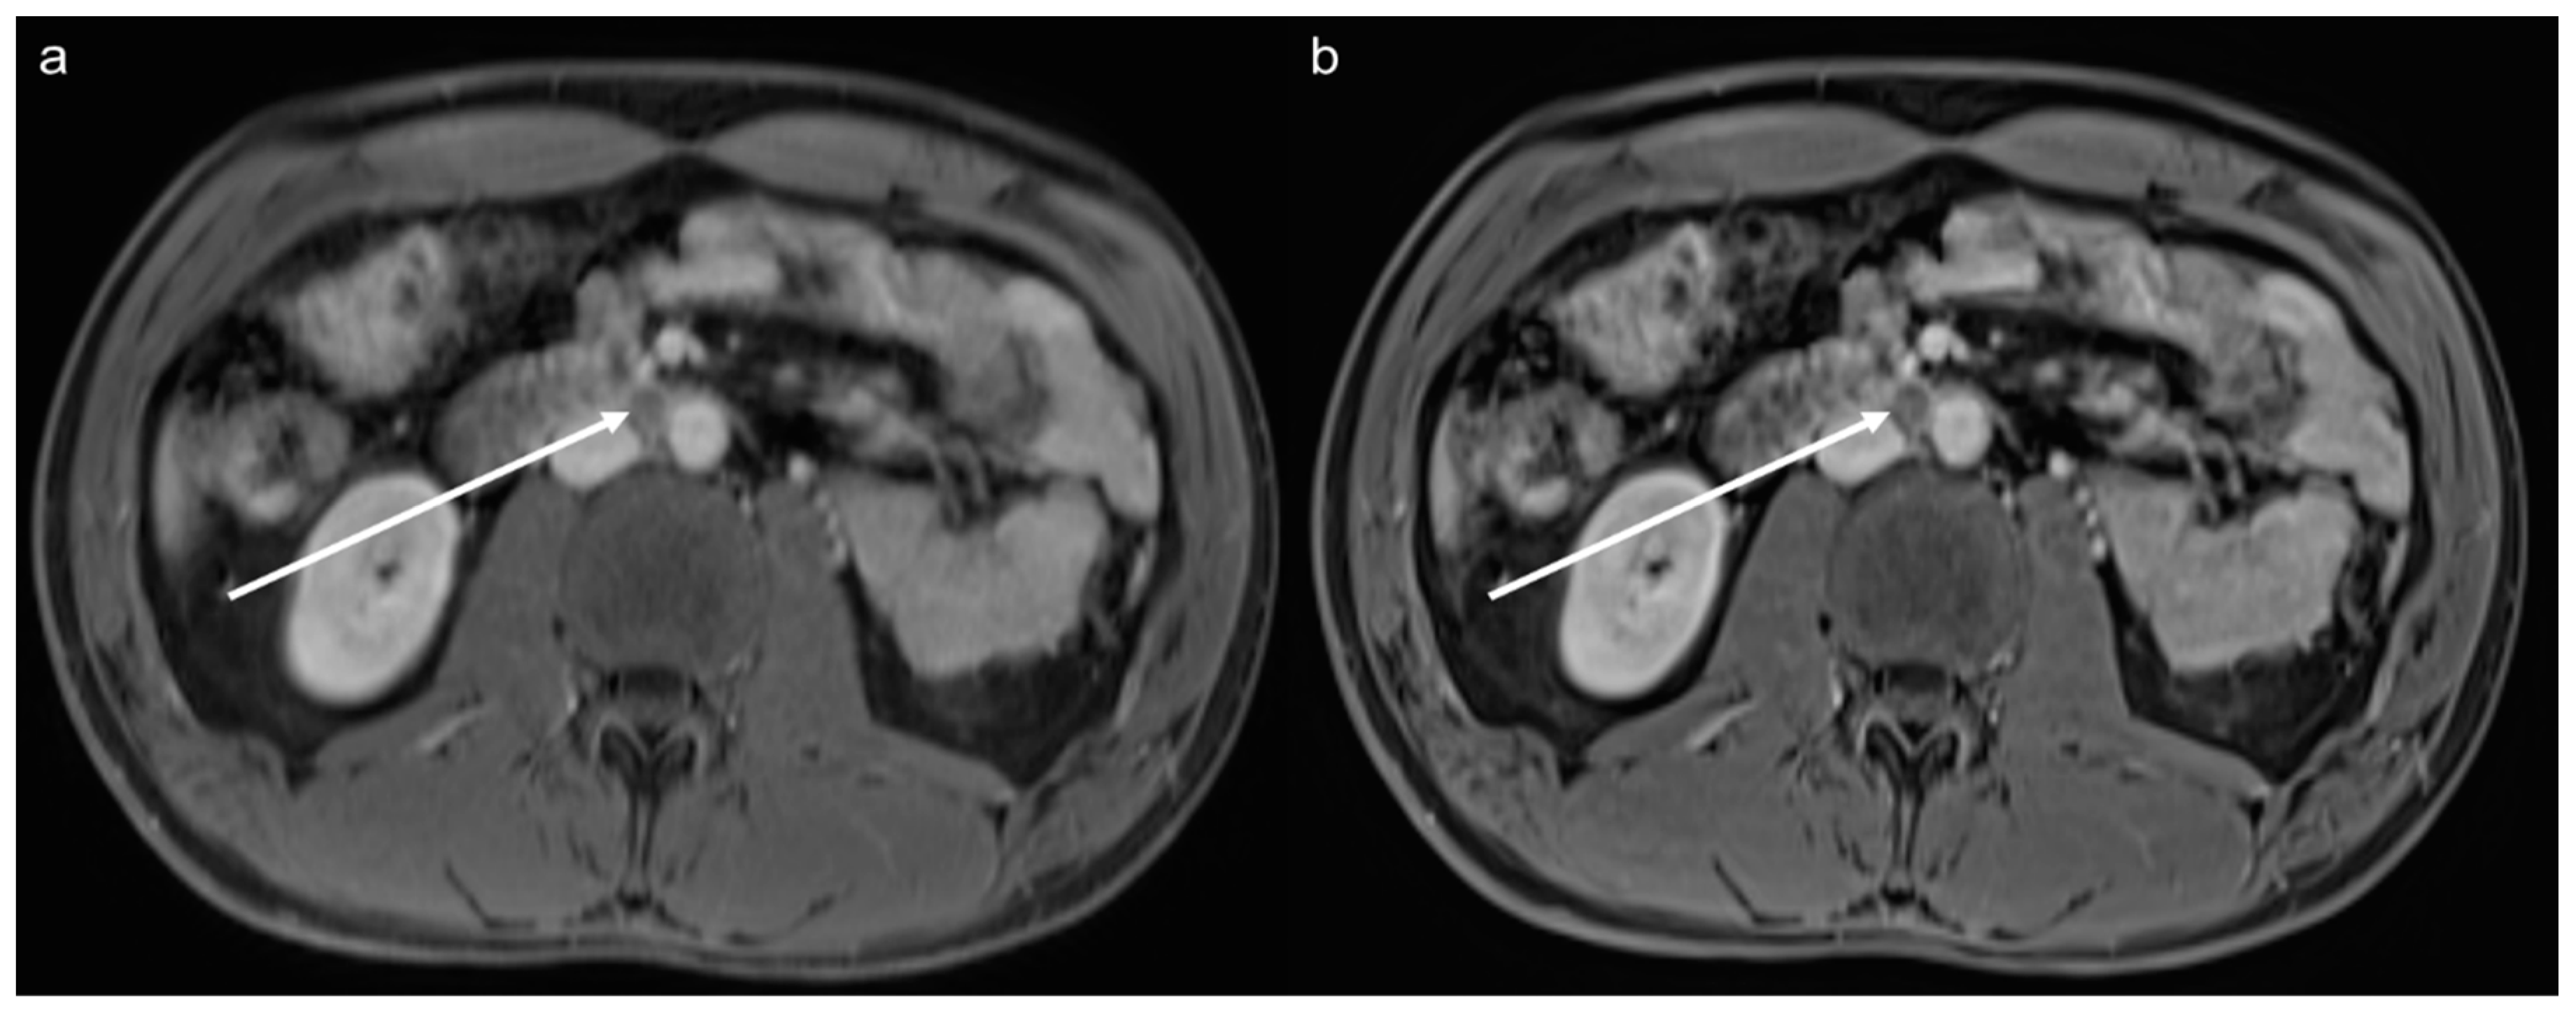

3.5. Lesion Assessment

3.6. Acquisition Time